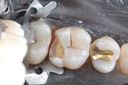

Scott Kanamori #31 pre-op

Scott Kanamori #31 amalgam removal

Scott Kanamori #31 prep

Scott Kanamori #31 finish

Scott Kanamori #31 finish buccal